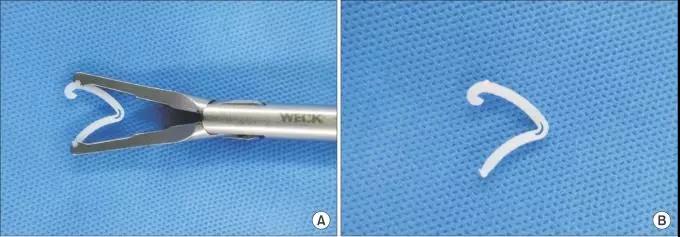

韩国蔚山大学医院外科Dong Jin Park医生3月在《外科治疗和研究年鉴》上发表一个案例报道,叙述了“血管止血夹静悄悄地侵蚀胃十二指肠吻合口”的过程。

一个58岁男人,因早期胃癌,接受了腹腔镜辅助远端胃切除术LADG及胃十二指肠吻合术。 术中,胃周血管,采用血管止血夹,我们通常称为Hem-O-Lok,进行钳夹止血。图中箭头所指,为血管止血夹夹在胃网膜右动脉上。

Hem-o-Lok血管止血夹,是腹腔镜手术常用的、替代结扎血管的方法。这种材料是不吸收的多聚化合物,具有惰性、绝缘、与CT和磁共振兼容,对病人安全的特点。